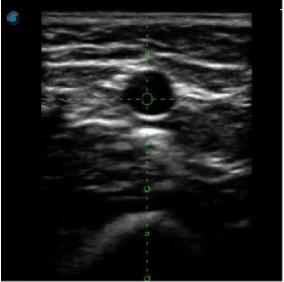

取卵臨床圖